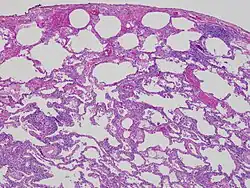

High magnification photomicrograph of a lung biopsy taken showing chronic hypersensitivity pneumonitis (H&E), showing mild thickening of the walls of the small air sacs by invasion of white blood cells. A multinucleated giant cell, seen within the walls of the air sacs to the right of the picture halfway down, is an important clue to the correct diagnosis. | |

Lung biopsy

Lung biopsies can be diagnostic in cases of chronic hypersensitivity pneumonitis, or may help to suggest the diagnosis and trigger or intensify the search for an allergen. The main feature of chronic hypersensitivity pneumonitis on lung biopsies is expansion of the interstitium by lymphocytes accompanied by an occasional multinucleated giant cell or loose granuloma.[7][22]

When fibrosis develops in chronic hypersensitivity pneumonitis, the differential diagnosis in lung biopsies includes the idiopathic interstitial pneumonias.[23] This group of diseases includes usual interstitial pneumonia, non-specific interstitial pneumonia and cryptogenic organizing pneumonia, among others.[7][22]

The prognosis of some idiopathic interstitial pneumonias, e.g. idiopathic usual interstitial pneumonia (i.e. idiopathic pulmonary fibrosis), are very poor and the treatments of little help. This contrasts the prognosis (and treatment) for hypersensitivity pneumonitis, which is generally fairly good if the allergen is identified and exposures to it significantly reduced or eliminated. Thus, a lung biopsy, in some cases, may make a decisive difference.